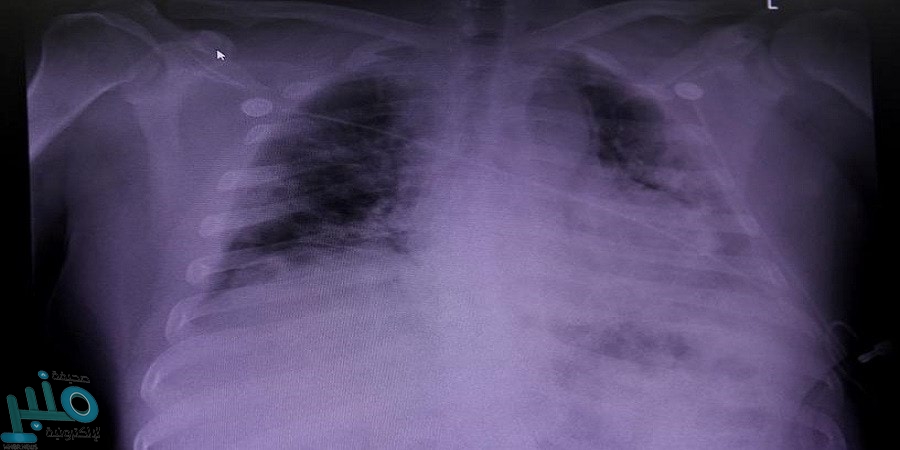

طور باحثون من جامعة نورث وسترن (NU) الأمريكية، منصة إلكترونية باستخدام برنامج الذكاء الاصطناعي ”التعلم العميق“، أطلقوا عليها اسم ”DeepCovid-XR“، بحيث يمكنها الكشف عن فيروس كورونا، من خلال تحليل صور الأشعة السينية للرئتين لدى المرضى، وذلك أكثر دقة وسرعة من الأطباء.

ووفقا لموقع ”The Express Tribune“ الإخباري، أثبتت التجارب أن خوارزمية التعلم الآلي تفوقت على فريق أخصائي الأشعة القطعية للصدر، عن طريق رصدها لفيروس كورونا المستجد في صور الأشعة السينية للصدر، وذلك أسرع بنحو 10 مرات، وأكثر دقة بنسبة 1-6% من الأطباء.

واستخدم الباحثون 17002 صورة أشعة سينية للصدر، لتطوير وتدريب واختبار الخوارزمية الجديدة، ومن بين تلك الصور، جاء 5445 من المرضى المصابين إيجابيا بفيروس كورونا.

وقارن الباحثون أداء المنصة مع أداء خمسة من أخصائيي أشعة وأمراض القلب والصدر، في تحليل 300 صورة عشوائية لمرضى من مستشفى ليك فورست الأمريكي.

واستغرق كل أخصائي أشعة ما يقرب من ساعتين ونصف إلى ثلاث ساعات ونصف الساعة لفحص هذه المجموعة من الصور، بينما استغرق نظام الذكاء الاصطناعي حوالي 18 دقيقة فقط.

وتراوحت دقة أخصائي الأشعة بين 76-81%، في حين كان أداء منصة ”DeepCovidD-XR“ أفضل قليلا بدقة بلغت 82%.